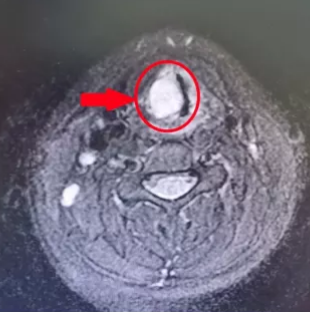

今年暑假,经人推荐,元元的父母带着她到杭州市中医院耳鼻喉科就诊。接诊医生详细问诊,通过完善视频喉镜和喉部增强MR检查,初步判断元元可能是患上了喉部肿瘤。由于瘤体的位置紧靠动脉和神经,就像一颗“定时炸弹”,医生立即将她收住入院,准备手术。

在视频喉镜下,医生精细操作,成功将肿瘤完整切除干净,且丝毫未损伤周围脏器血管,术中几乎没有出血。

术后病理结果显示,元元的患上的竟是非常罕见的咽部神经鞘瘤。耳鼻喉科主任陈志凌介绍,咽部神经鞘瘤好发于咽后壁及侧壁,虽大多为良性肿瘤,但会压迫咽喉、气管,可引起呼吸困难或窒息,包绕咽喉部引起吞咽困难等。好在元元手术及时,随着新学期的临近,她的康复也非常顺利。